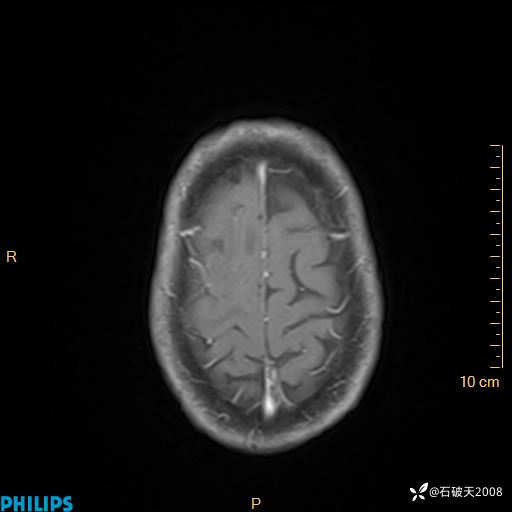

增强轴位

增强矢状位

增强冠状位